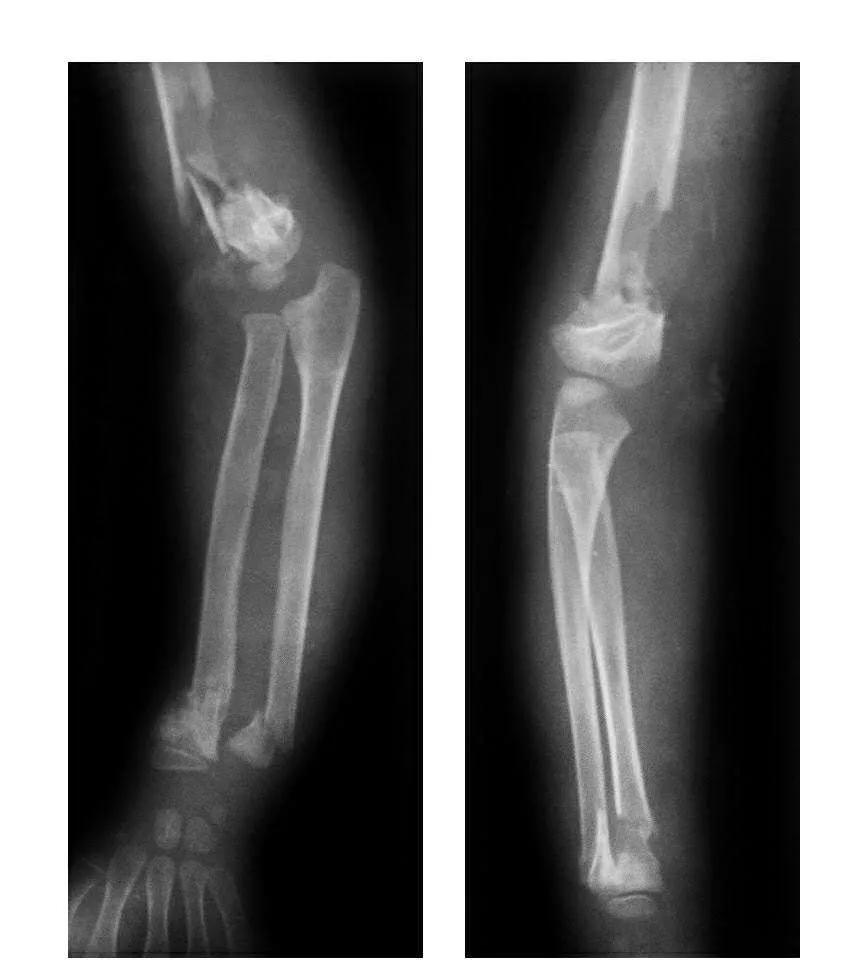

肘部损伤合并同侧前臂远端骨折

例1:肱骨髁上伸展型骨折并科勒斯骨折。

例2:肱骨髁上伸展型骨折并尺桡骨远端骨折。

例3:肱骨髁上屈曲型骨折并桡骨远端骨骺滑脱。

例4:肱骨髁上骨折并桡骨下端骨折。

例5:陈旧性肘关节后脱位合并桡骨远端骨骺滑脱及尺骨下段骨折。

例6:肱骨外髁骨折合并桡骨远端骨骺滑脱并尺骨下段骨折。